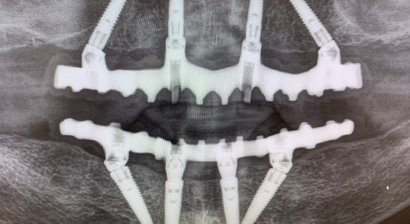

Die rein implantologischen und kieferchirurgischen Leistungen der Ordination reichen von dreidimensionalen Röntgenaufnahmen ( 3D-Röntgen, DVT ), abdruckfreiem Scanner und Computerplanung ( X-Guide ) über neue evidenzbasierte Methoden des Knochenaufbaus bis hin zu Vollnarkose oder Sedoanalgesie und decken dabei das gesamte Spektrum der Implantologie inklusive festsitzender Versorgungen auf Implantaten mit Sofortversorgung ( All-on-4, Feste Zähne an nur einem Tag ) ab. Die Praxis wurde eben zum Excellence Center in Gold für die All-on-4 Behandlungsmethode zertifiziert und ausgezeichnet, als nur eines von 2 Centers in Österreich. Mehr an Info dazu unter www.allon4.at

Sofortimplantate und Sofortbelastung sind unser Spezialgebiet und die Wiederherstellung eines komplett zahnlosen Kiefers unsere häufigste Behandlungsart.